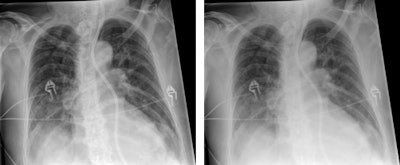

The emphasis of Philips' researchers has been on developing technologies for improving diagnostic quality while eliminating inefficiencies when using mobile digital radiography systems at the patient's bedside. The new SkyFlow scatter correction algorithm reduces the effect of scattered radiation for nongrid bedside chest exams, allowing the operator to obtain DR images with grid-like contrast, but avoiding the time and effort involved in attaching and detaching a grid.

On the GE Healthcare stand, its representatives are keen to discuss new evidence showing the clinical value of its long established digital tomosynthesis technology, VolumeRAD. A recently completed international multicenter clinical trial has demonstrated that the product offers improved detection and management of patients with lung nodules compared with conventional radiography – with a 7.5 times increase in sensitivity for nodules between 4 mm and 6 mm diameter compared with standard x-ray. The device is reportedly 3.6 times more sensitive than conventional two-view computed radiography, without decreased specificity of detection of small lung nodules in the range of 3 mm to 20 mm in diameter.